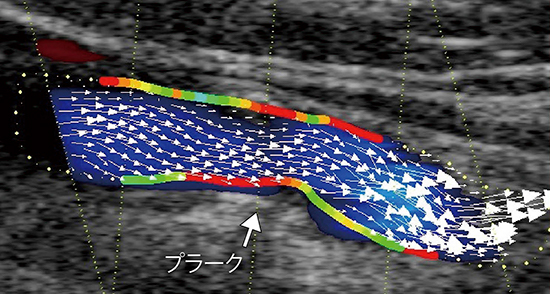

VFM Vascularの実際の画像を見ると,分岐部血流(図2)や複雑な血流(図3),内頸動脈プラーク壁にかかるWSSが血流のベクトルとともに可視化されている(図4)。WSSの数値化も可能なため,血流が局在するプラークに与える影響をWSSとして定量化できると考えている。

図3 内頸動脈起始部のプラークと血管屈曲による複雑な血流ベクトル